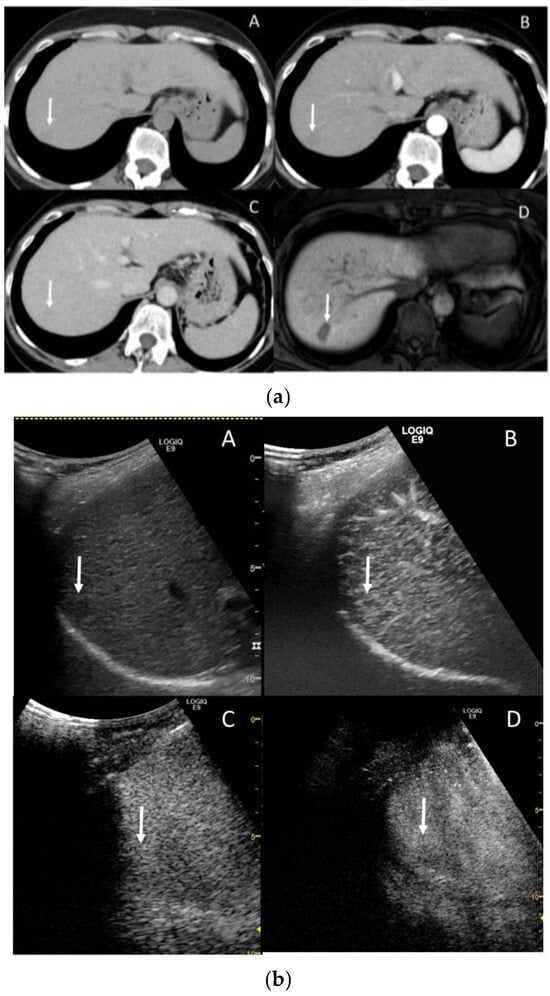

3.1. CT and MR Features of Liver Cirrhosis (LC)

3.2. Ultrasonography (US) and Magnetic Resonance Elastography (MRE)

3.4. Extracellular Volume Fraction (ECV)

3.5. Extracellular Volume Fraction (ECV)

3.6. Gadoxetic Acid Enhanced MRI (EOB-MRI)